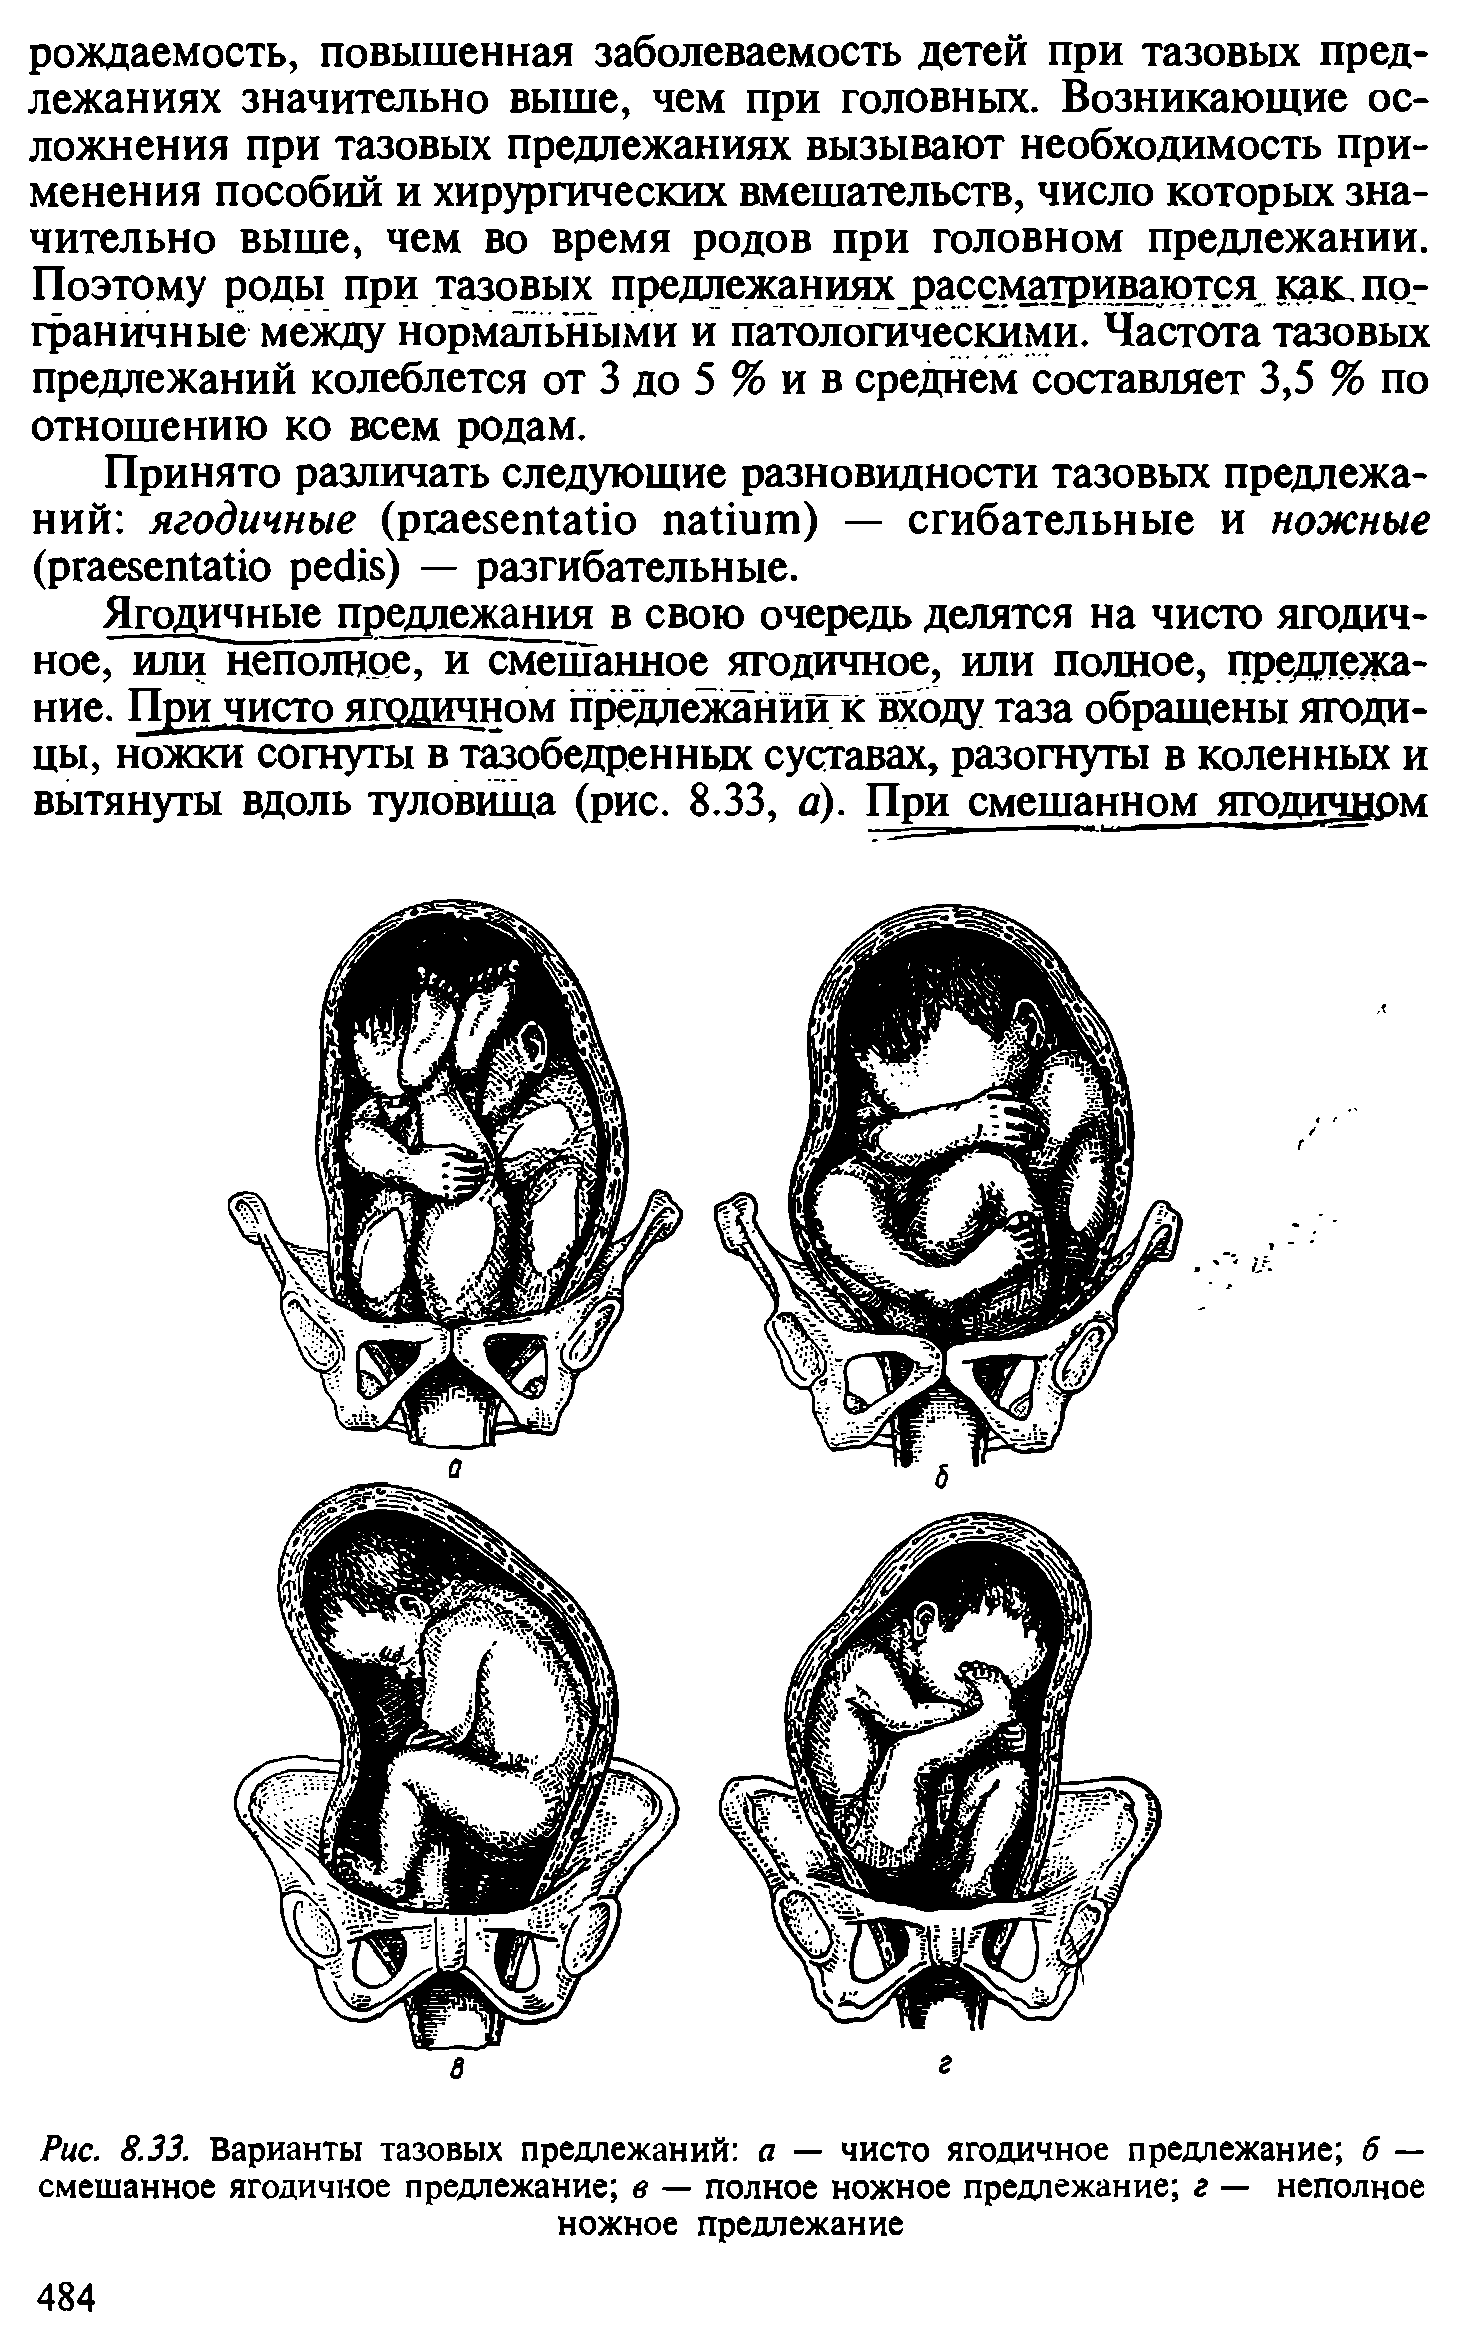

Breech.webp)

Живот с ягодичным предлежанием

External Cephalic Version(ECV) technique for Breech Baby

Метод Цовьянова при ягодичном предлежании

Рождение ребенка в тазовом предлежании

Первый момент биомеханизма родов при тазовом предлежании